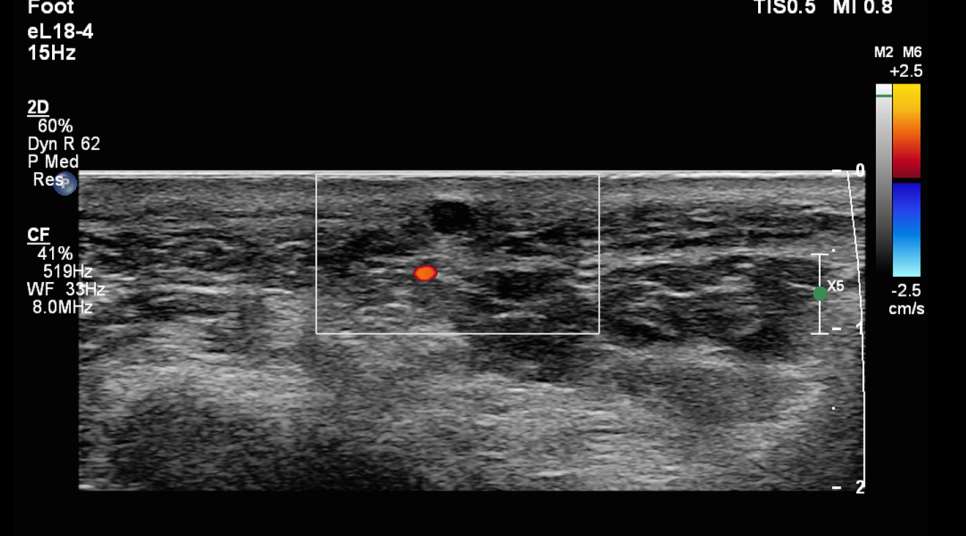

환자분의 초음파 사진입니다.

작은 원 모양의 혹이 관찰됩니다. 크기는 약 0.5cm 정도입니다.

가로, 세로 비슷한 크기입니다. 혈관이 지나가거나 신경이 지나가는 것도 없습니다. 대부분의 발바닥의 혹은 섬유종이라고 합니다. 크기가 좀 더 크고 통증이 없습니다. 그냥 굳은살과 비슷한 느낌이라고 보시면 됩니다.

하지만 이것은 다른 것입니다. 그럼 뭐냐?

표피낭종 입니다.